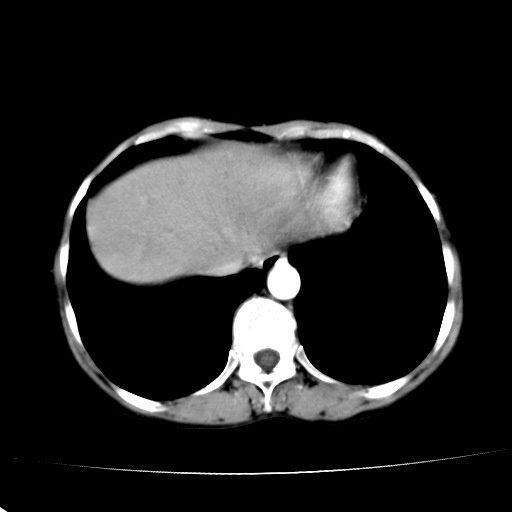

以下是引用jiangjing在2008-6-3 13:36:00的发言:[br]支持 胰头癌------肝内外胆管扩张,胰管扩张,胰头增大,增强见结节状轻度强化影,双管征明显

以下是引用卜一在2008-6-3 14:40:00的发言:[br]支持:胰头癌!(肝内外胆管扩张,胆囊高度扩张,胰管扩张,胰头增大,增强见结节状强化,明显低于胰腺强化密度,并明显见双管征)

以下是引用dyqct在2008-6-3 14:54:00的发言:[br]支持 胰头癌伴肝内外胆管扩张,胰管扩张,胰头增大,增强见结节状轻度强化影,双管征明显。肠系膜上静脉已受侵(已不能手术),建议离子植入治疗吧。